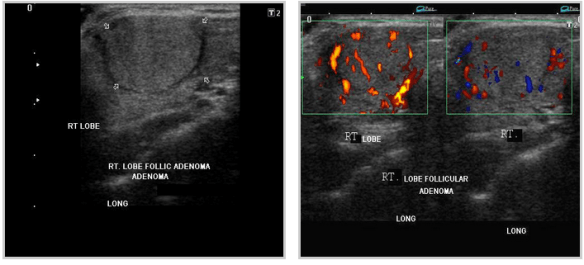

FOLLICULAR ADENOMAthyroid_follicular adenomas